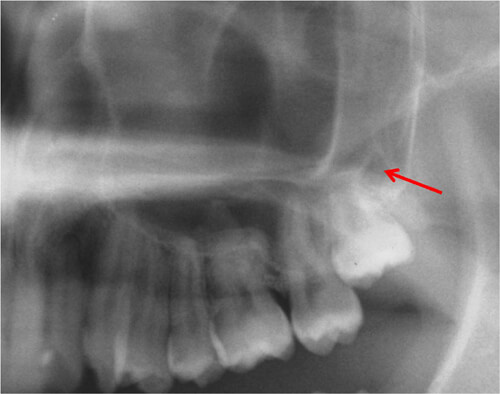

②下顎水平埋伏智歯

下顎の智歯(親知らず)が水平に埋まっている状態。